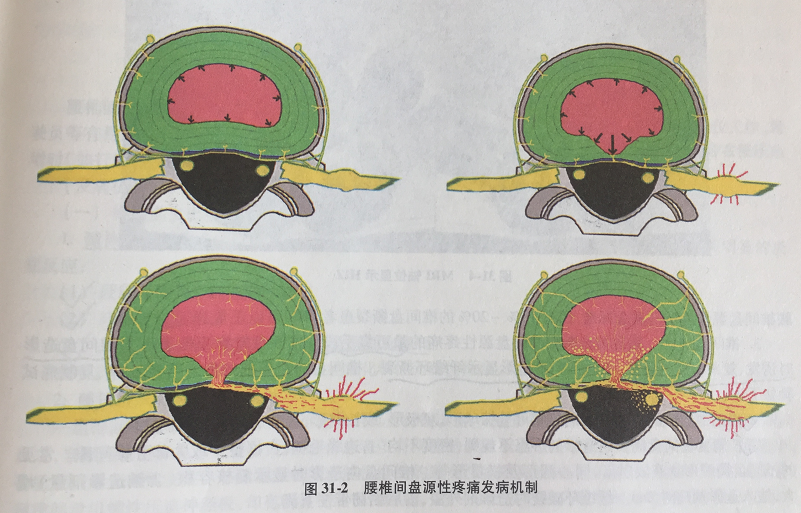

1、神经长错了地方:

正常纤维环外 1/3 几乎没有神经分布,在高度退变的椎间盘组织中,纤维环内层甚至髓核的内部也出现了神经分布,这些异常的神经末梢被认为与疼痛的产生密切相关。手术已经证实:刺激纤维环外层及后纵韧带可以诱发腰痛。

2、炎症刺激:

髓核是全身最大的无血管组织,当内层纤维环破裂后,中央退变的髓核可作为抗原刺激机体产生免疫反应,产生许多炎症介质(IL-6、NO、TNF等),它们沿纤维环裂隙扩散,使神经末梢处于“点火”状态,轻微机械刺激即可产生剧烈疼痛。

3、力学失衡:

腰椎间盘髓核变性致纤维环应力分布失衡和内层纤维环撕裂,久坐、前倾、搬重物时,髓核向后推移进一步牵拉敏感的外层纤维环,形成“化学致敏 + 机械牵拉”的恶性循环。